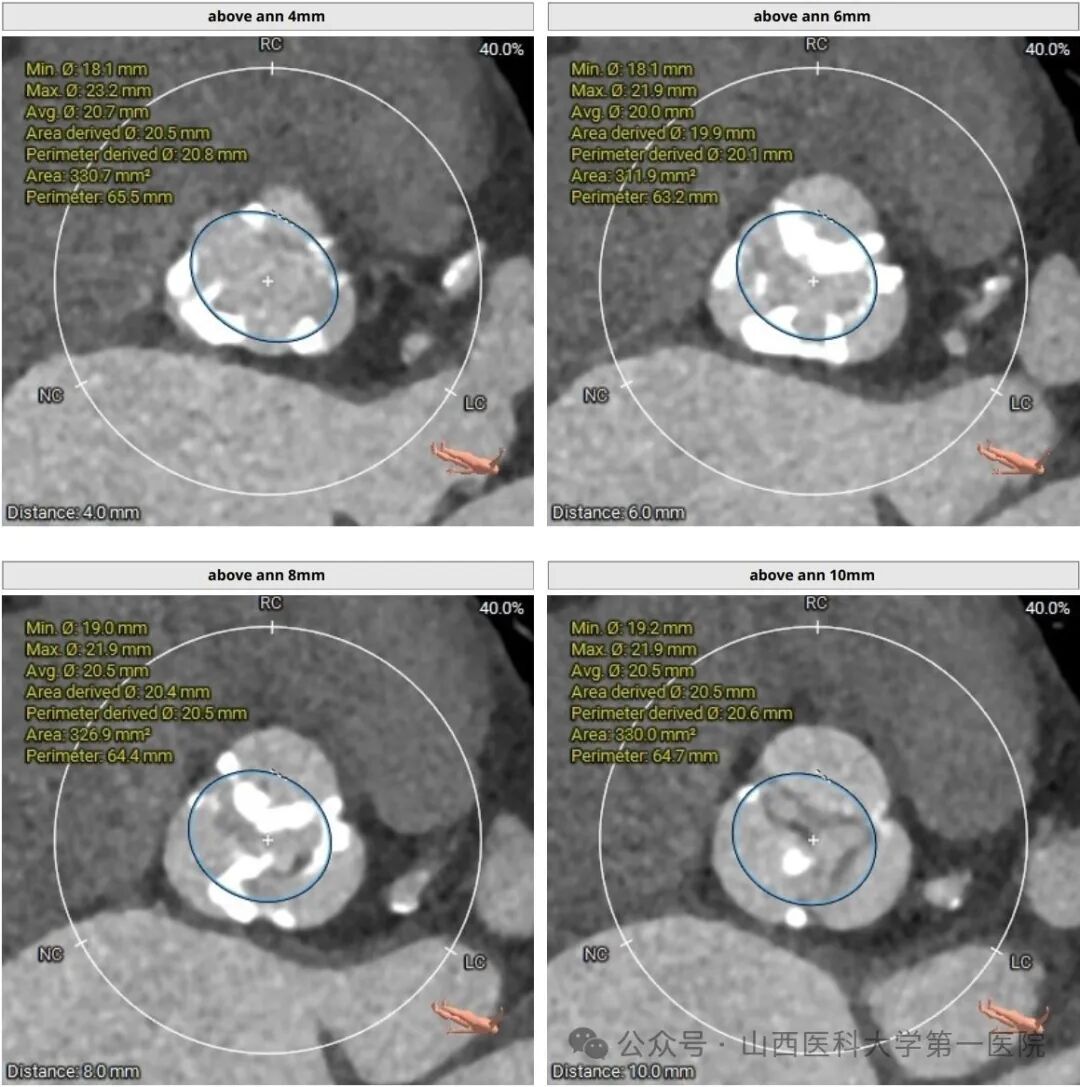

两例患者均为高龄女性,第一例患者胸腹CTA及心脏彩超提示:主动脉瓣重度狭窄,主动脉瓣及主动脉钙化严重,合并冠心病,既往有高血压及脑梗死病史;第二例患者胸腹CTA及心脏彩超提示:主动脉瓣呈二叶畸形,重度钙化伴偏心性狭窄,合并重度贫血。两例患者病变严重,对医生介入治疗技术要求极高,其中第一例患者主动脉瓣及主动脉血管钙化严重,介入手术过程中出现血管损伤、瓣周漏、重要脏器栓塞及脑卒中的风险极高,第二例患者主动脉瓣为二叶畸形,偏心性钙化严重,导丝通过及其困难,主动脉弓成角明显,介入手术致瓣周漏、瓣膜移位、血管损伤的风险极高。

在心脏大血管外科结构性心脏病介入团队的默契配合及多学科专业人员的大力协助下,两例患者均顺利完成经导管主动脉瓣置换术(TAVR),释放瓣膜后主动脉根部造影示:主动脉瓣支架瓣膜形态良好,经食道超声显示主动脉瓣收缩期最大流速约1.5m/s,平均压差小于10mmHg,术后患者恢复顺利,已于近日出院。